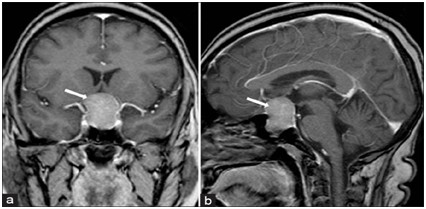

Синдром пустого турецкого седла на МРТ

При этой патологии на снимках, полученных при МРТ, виден истонченный, распластанный по дну турецкого седла гипофиз. Цистерна зрительного перекреста при этом провисает (по-научному – пролабирует) в полость данного костного образования. На томограммах, выполненных в передне-заднем направлении, железа напоминает формой серп, толщина которого не превышает 2-3 мм.

Опухоли области турецкого седла и зрительного перекреста на снимках МРТ

В области гипофиза выявляются новообразования, варьирующиеся по размерам:

- до 10 мм в диаметре – микроаденома;

- 10-30 мм в диаметре – макроаденома; опухоль менее 10 см также может носить это название, но при условии распространения за пределы седла;

- мезоаденома – разновидность макроаденомы размером 10-22 мм, расположенная в области турецкого седла, не выходящая за его пределы;

- свыше 30 мм – гигантская аденома.

Помимо аденомы в хиазмально-селлярной области могут быть диагностированы менингиома, краниофарингиома, герминома и некоторые другие виды опухолей, характеризующиеся рядом признаков на томограмме.

Новообразование гипофиза может локализоваться в турецком седле, прорастать в кавернозные синусы, желудочки мозга, пазуху основной кости, цистерну моста, носовые ходы. Все это на изображениях МРТ, конечно, будет заметно.

Косвенными признаками опухоли гипофиза являются:

- неоднородность структуры железы в каком-то одном месте (то есть не диффузная, а очаговая);

- асимметрия ее;

- смещение воронки от срединной линии;

- деформация дна турецкого седла.

На основании только этих данных диагноз поставить невозможно, их необходимо рассматривать в комплексе с клинической картиной и результатами обследования, проводимого в динамике.